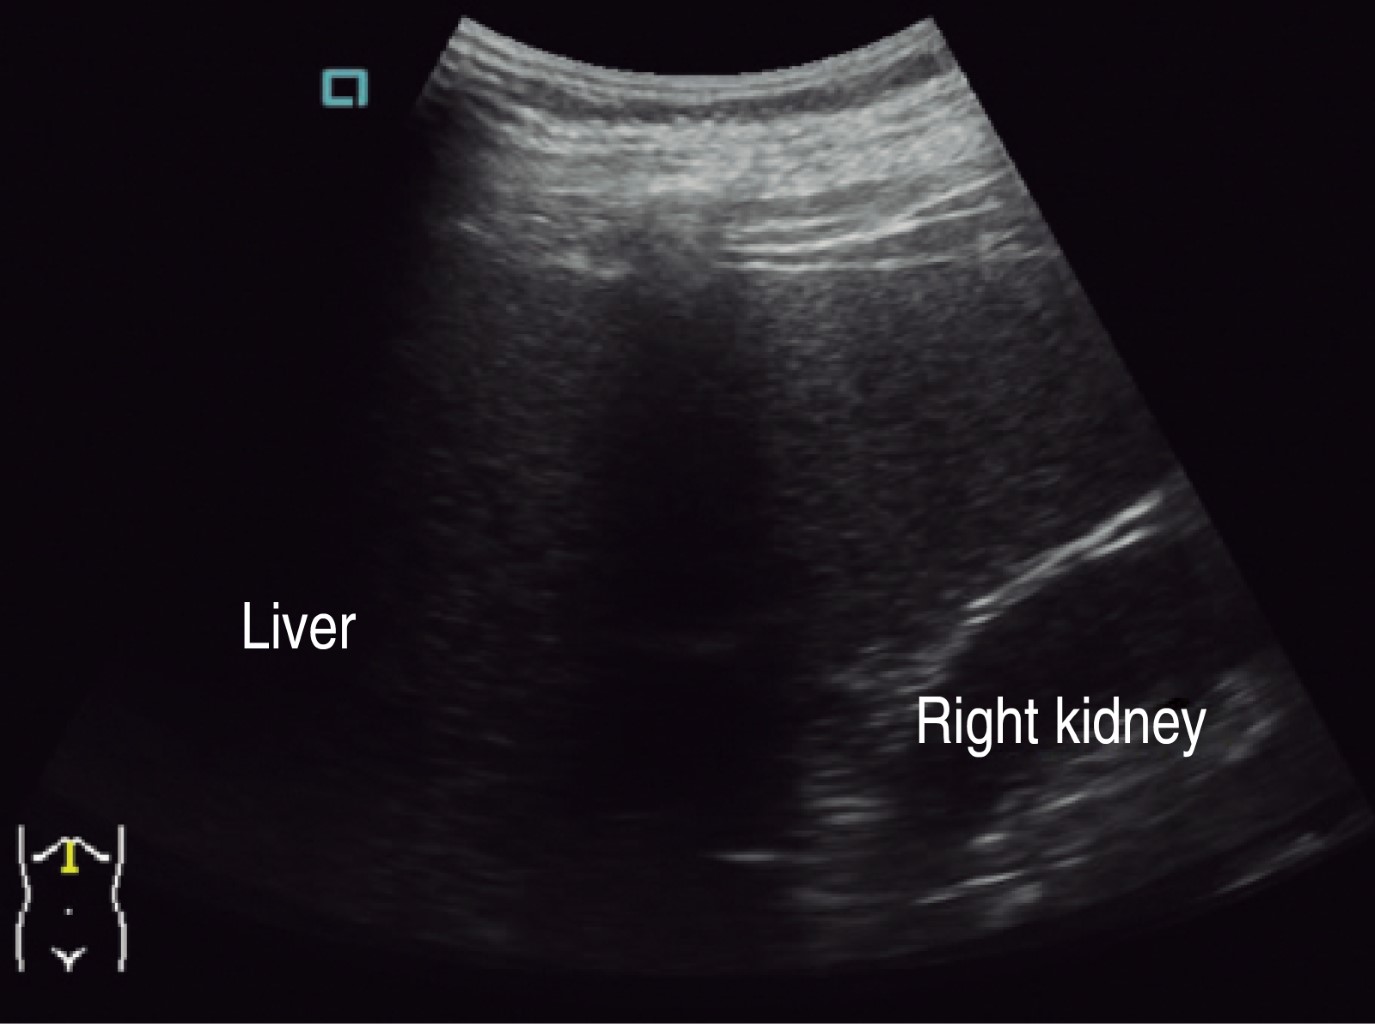

An ultrasound scan done in March reports liver of normal size, shape, and situation with an irregular lower right border, of heterogeneous echogenicity due to the presence of a rounded shape anechoic mass with well-delimited borders and thin walls suggestive of a simple cyst (Figures 1 and 2).

Figure 7